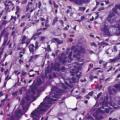

La classification des cancers gastriques est complexe puisque plusieurs types histologiques peuvent coexister au sein d’une même tumeur. Par ailleurs, différentes classifications histologiques sont utilisées en pratique courante et dans les études, avec des valeurs pronostiques variables. L’adéno- carcinome gastrique à cellules indépendantes (ADCI) est défini comme étant un adénocarcinome gastrique comportant un contingent majoritaire (plus de 50 % de la tumeur) de cellules isolées ou de petits groupes de cellules disséminées dans un stroma particulièrement fibreux et contenant de la mucine en intracytoplasmique (fig. 1) [v. encadré2, 3]. Il a une épidémiologie et un pronostic propre. Il est, en effet, plus fréquemment observé chez les sujets jeunes et est diagnostiqué à un stade plus avancé que les autres types histologiques. Il est également associé à un pronostic plus sombre, que ce soit sur la survie globale ou la survie sans récidive.4

De même, une confusion fréquente est faite entre le type histologique ADCI et la linite gastrique. Cette dernière est définie macroscopiquement, en anatomopathologie, en endoscopie (fig. 2) ou en imagerie (fig. 3), par un aspect épaissi et rigide de la paroi gastrique. L’aspect de linite est fréquemment associé au type histologique ADCI, comme cela a été noté dans une série de 27 linites gastriques analysées par deux anatomopathologistes différents. P armi ces linites, 21 étaient des adénocarcinomes gastriques à cellules indépendantes et 6 d’autres types histologiques selon la classification de l’OMS. Après une troisième lecture des lames, il apparaissait que 4 tumeurs avaient un contingent minoritaire de cellules isolées (< 50 %) et 2 tumeurs étaient des adénocarcinomes tubulaires.3